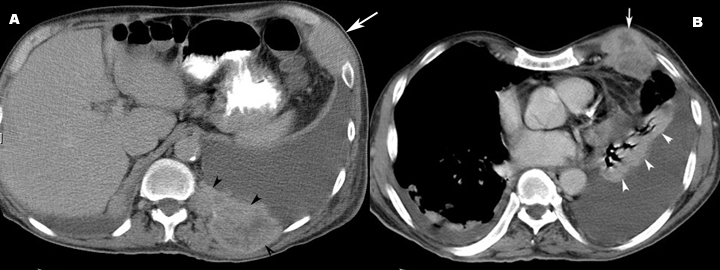

• In CT you can easily recognize masses in the presence of effusion.

• Mass in chest wall in multiple locations.

• White arrowheads point to collapsed left lower lobe.